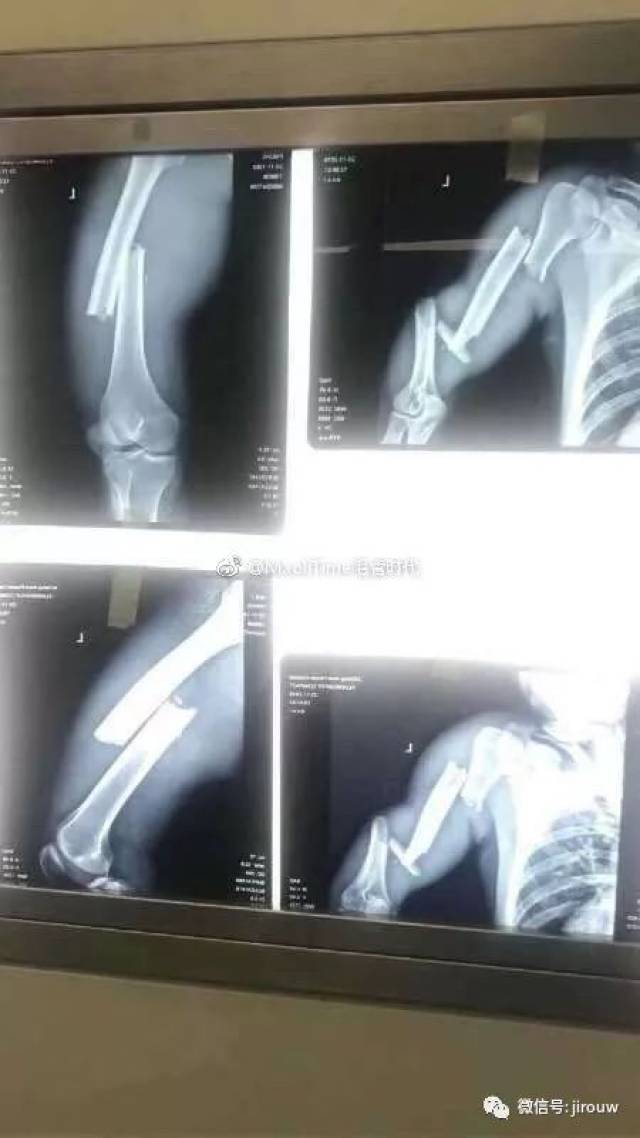

手骨断裂的照片

手骨断裂的照片,肋骨骨皮质断裂图片